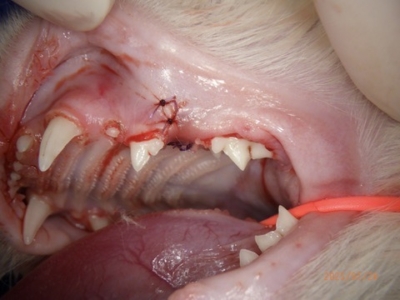

左下顎は中央に重なって生えている過剰歯があります。レントゲンで確認しても、乳歯ではなく永久歯と考えられました。これらは過剰歯と呼ばれ、通常より本数が多く歯が生えてきます。かみ合わせが悪くなり、また歯間が狭くなり歯垢がつき、歯周病になりやすいです。そのため、不必要と思われる歯を抜歯しました。また、歯肉の増殖している部分を一部切り取り病理検査用の検体とし、それ以外の部分はメスで切除し正常に近い歯肉の形状に近づけました。

抜歯後は必ずレントゲン写真で残根がないか確認しています。

術後二週間での再診です。だいぶすっきりしました。病理検査の結果では「慢性歯肉炎」で、年齢から考えると若年性歯肉増殖性歯肉炎という診断となります。

左側

右側。縫合糸が一部残っている

正面